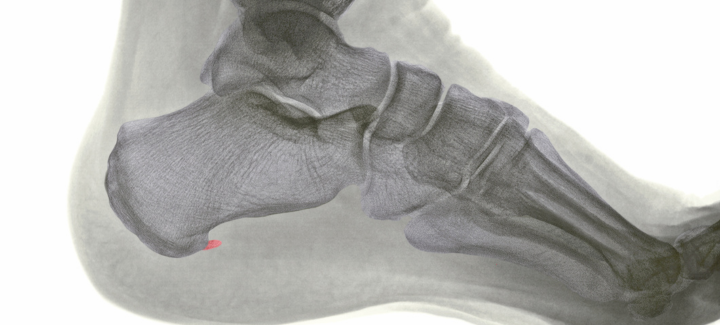

El espolón calcáneo es un crecimiento óseo anormal en la zona de apoyo del talón. Se desarrolla debido a una tracción continuada de la musculatura y la fascia plantar, que se inserta en el talón. Esta tracción repetitiva provoca microdesgarros en el tendón, y como respuesta, el cuerpo genera depósitos de calcio para frenar el daño. Con el tiempo, estos depósitos forman un saliente óseo conocido como espolón.

Para una confirmación definitiva, se suele realizar una radiografía del talón. En la imagen, se podrá observar un «pico»; prominente en la parte inferior del calcáneo, lo que confirma la presencia del espolón.